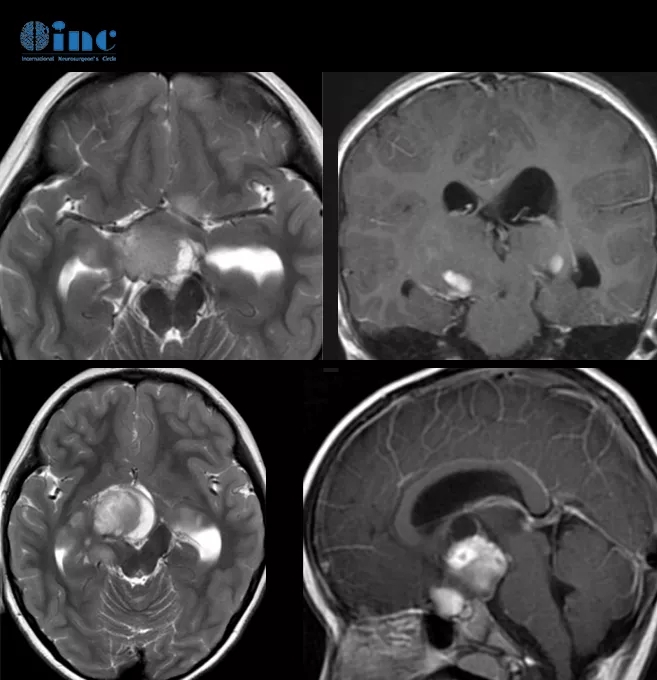

康康的術前MR影像

康康的術前術后MR影像對比